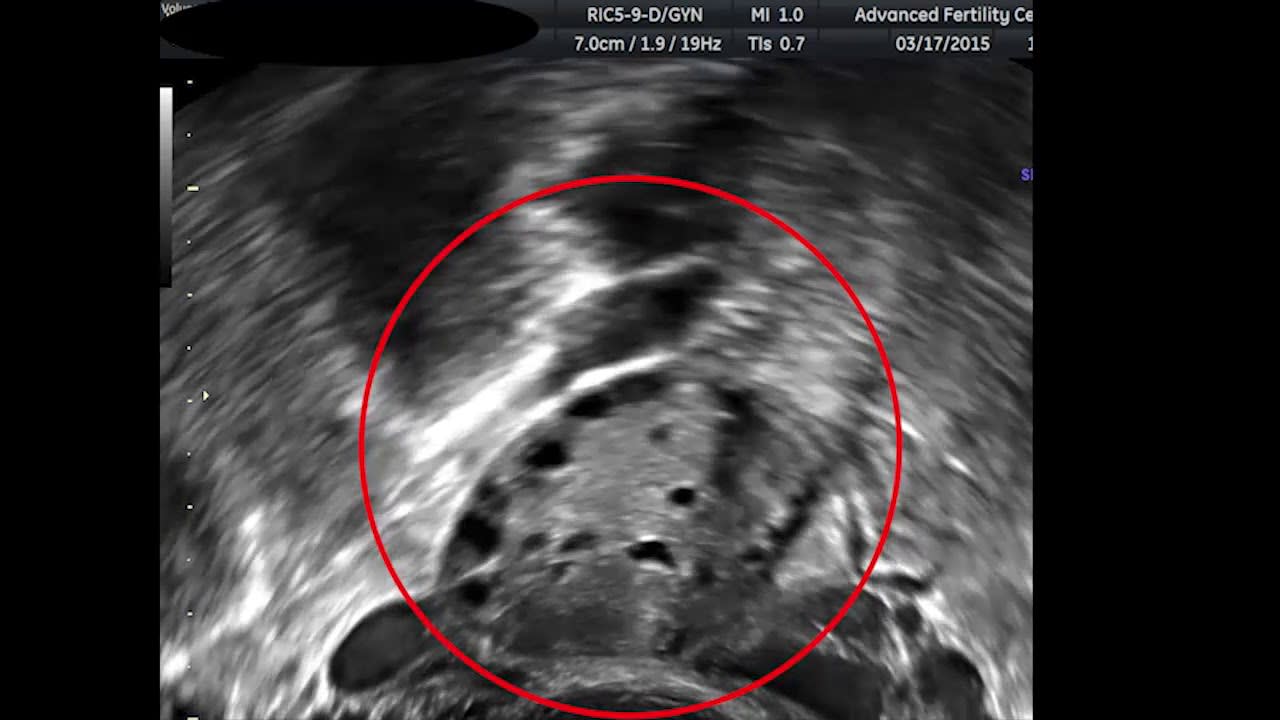

Another lower-cost but not free thing you can do is assess your likely egg production by undergoing the very first part of IVF; a consultation and ovarian ultrasound. This ultrasound is performed right at the very start of the IVF process and usually costs less than $1000. Ovarian reserve and antral follicle count are strongly correlated with the expected number of mature eggs you or your female partner will produce after hormonal treatments. If you’re willing to do embryo selection in theory if the gain is large enough, this can be a relatively inexpensive way to reduce the uncertainty about the benefits of the procedure.